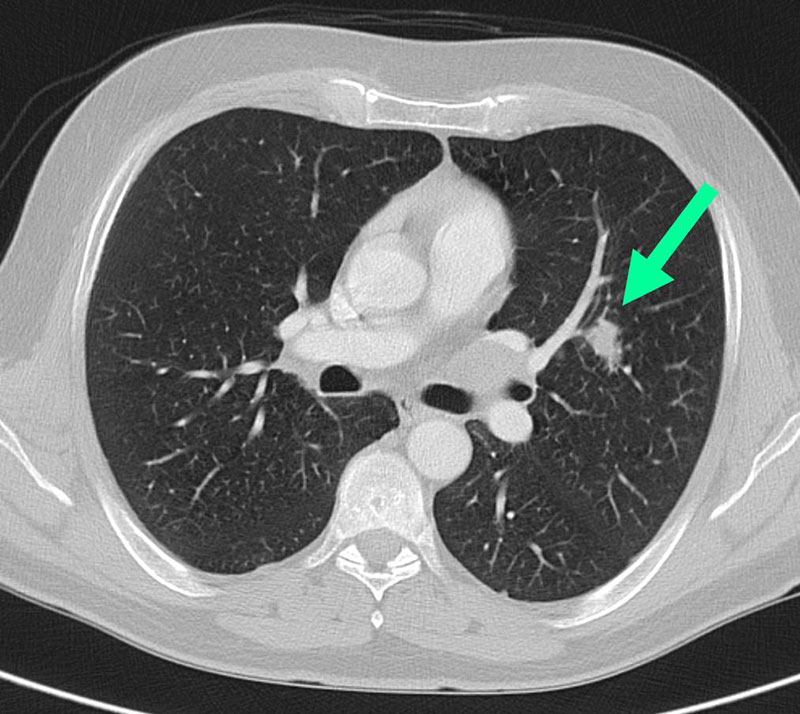

2. Computertomographie ("CT")

Diese Weiterentwicklung der Röntgentechnik liefert mit ihrem rotierenden Bildaufnahmesystem dünne Schichten und dreidimensionale Darstellungen der Lunge. Während bei der einfachen Röntgenaufnahme in der Überlagerung von Herz und Rippen kleinere Tumore unerkannt bleiben können, werden sie mit der CT sicher erfasst und können exakt vermessen werden. Im hochauflösenden CT (High resolution CT = HRCT) wird die Lungenfeinstruktur Schicht für Schicht millimetergenau erkannt und analysiert - fast wie im Mikroskop. Eine Wissenschaft für sich, und auch für erfahrene Radiologen immer wieder eine Herausforderung, ist die Erkennung von Lungenerkrankungen aus dem HRCT-Muster, z.B. bei der Lungenfibrose. Unsere modernen CT-Geräte stehen hierzu an allen Standorten der Radiologie Darmstadt zur Verfügung.

Lungenkarzinom im CT

kleines Lungenkarzinom im CT

(Zum Vergrößern bitte anklicken)